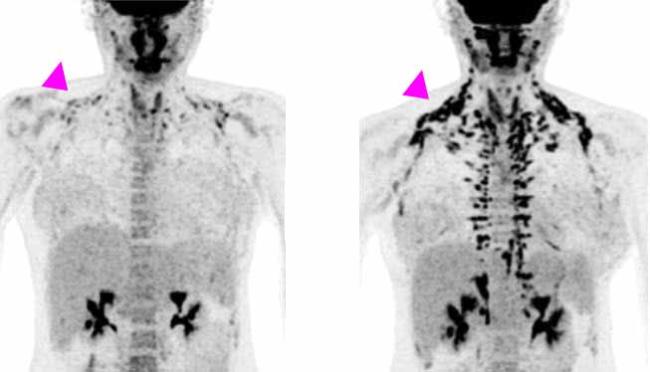

All of the women underwent positron emission tomography (PET)/CT scanning before treatment and at the end of the study, to measure brown fat activity. The researchers also measured the women's metabolism, cholesterol and other markers of heart health, and blood sugar and insulin sensitivity (the ability to use insulin properly and control blood sugar levels). Results appeared on January 21, 2020, in the Journal of Clinical Investigation.

After four weeks of treatment, the women’s metabolism at rest was almost 6% higher, although their weight or overall body composition—the ratio of fat to muscle—hadn’t changed. Brown fat activity, as measured by PET/CT, also increased during the study. The largest changes were found in women who had less brown fat activity to begin with.